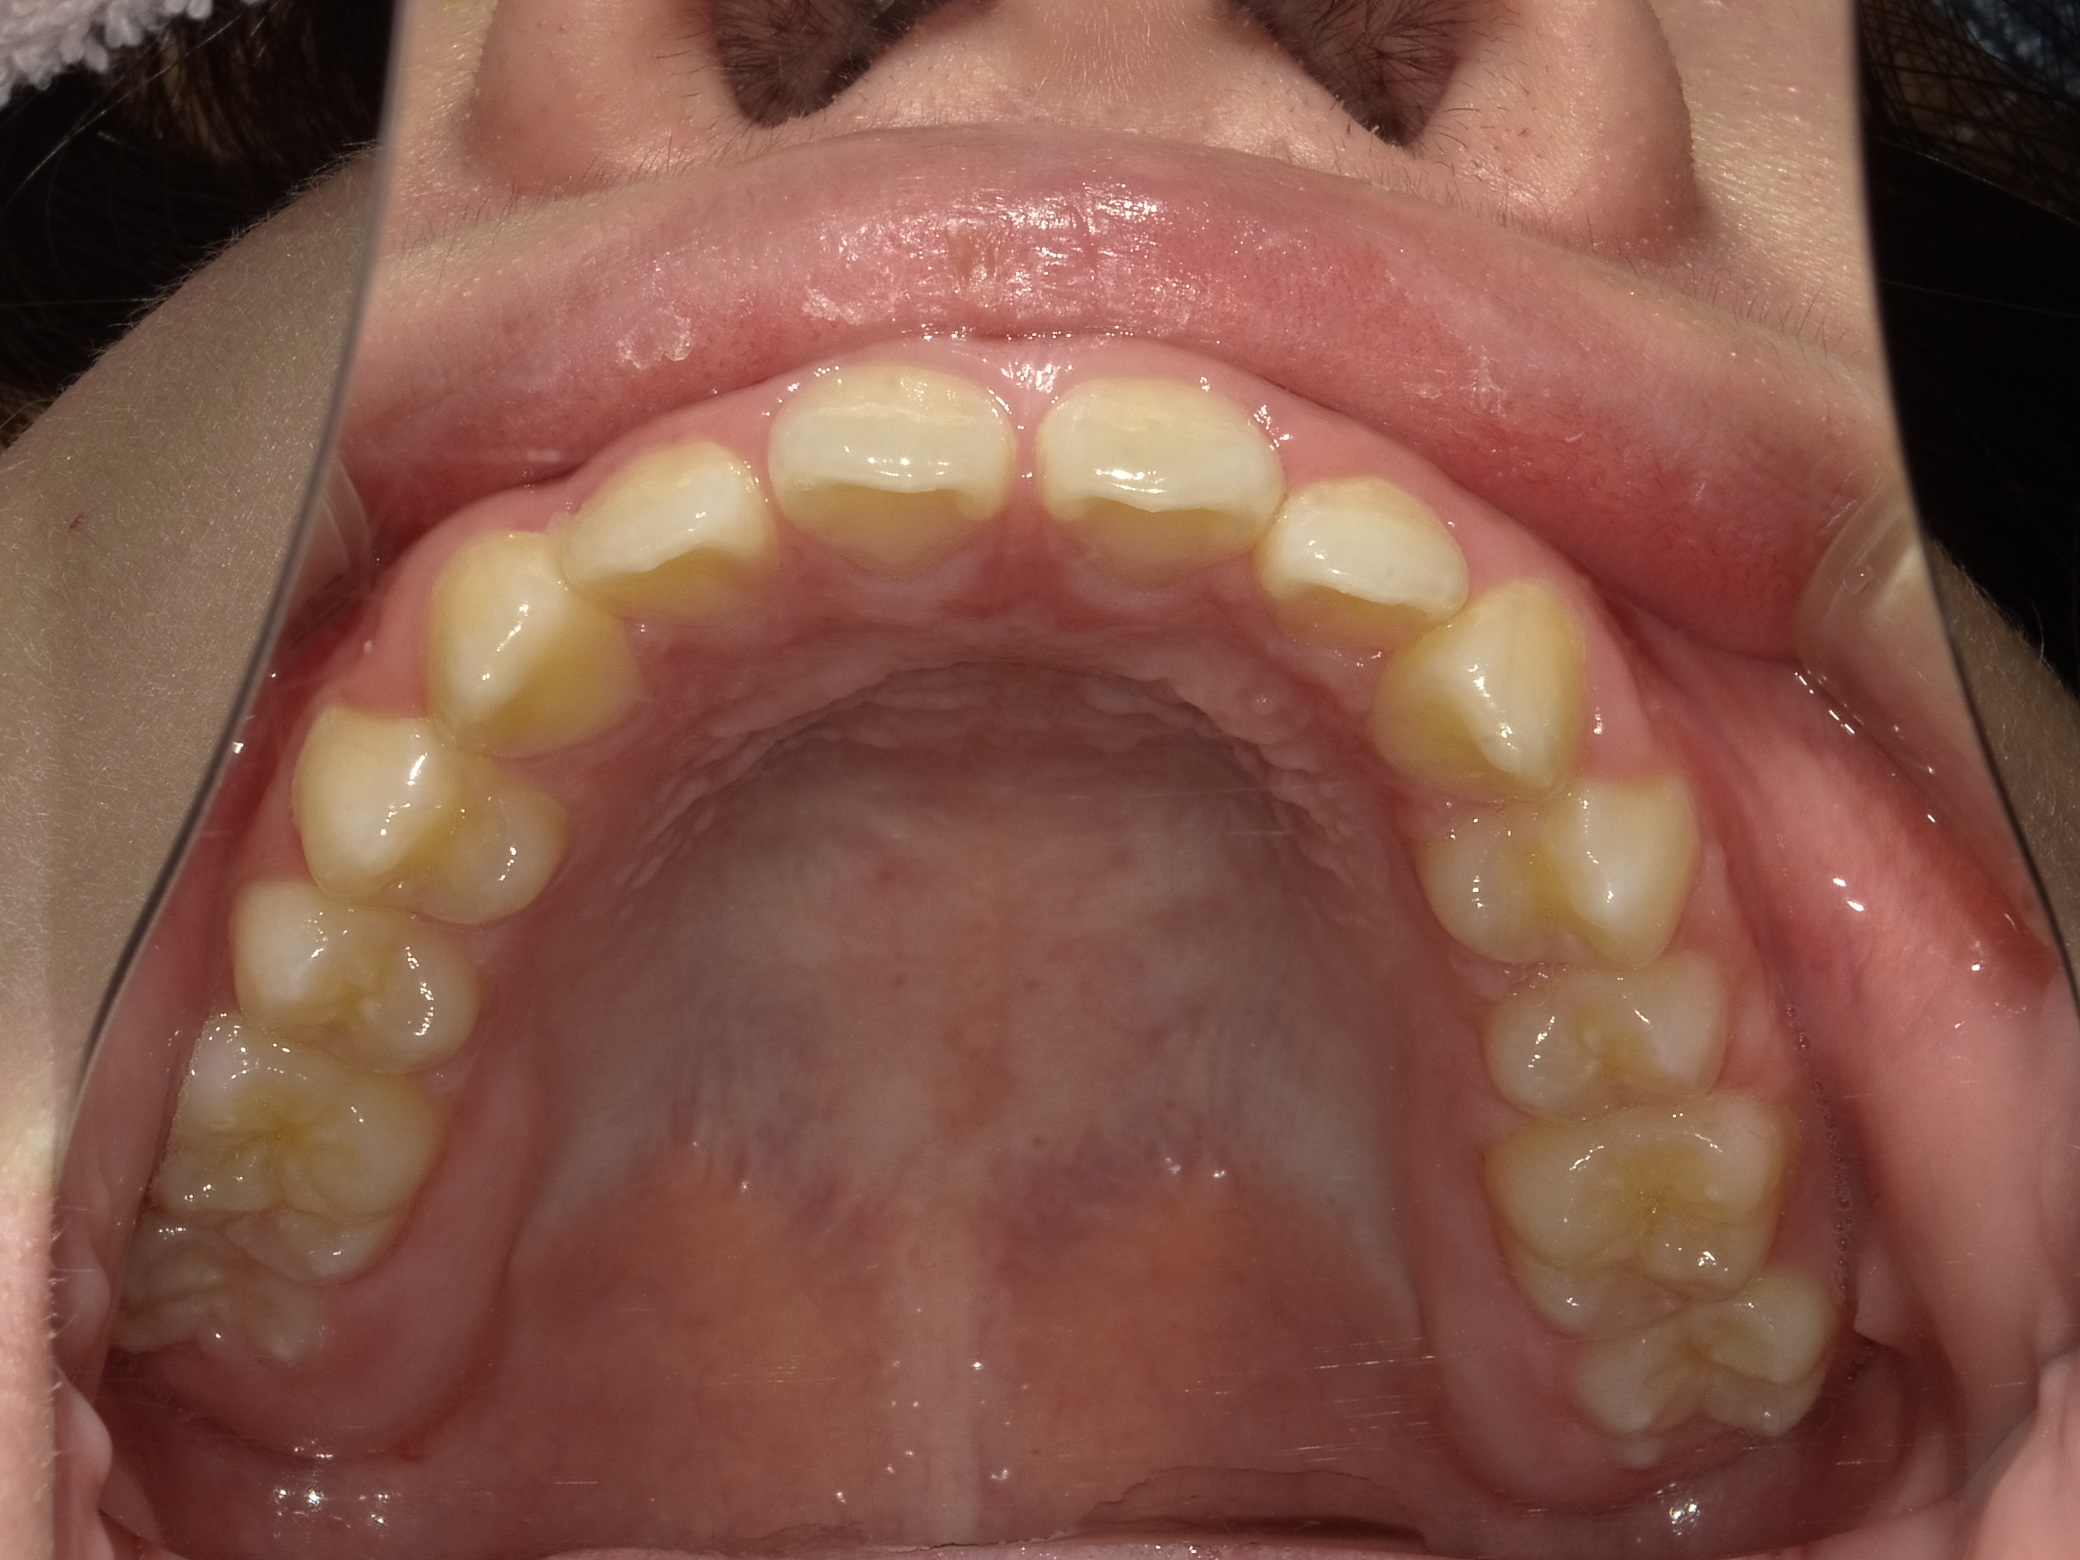

上顎